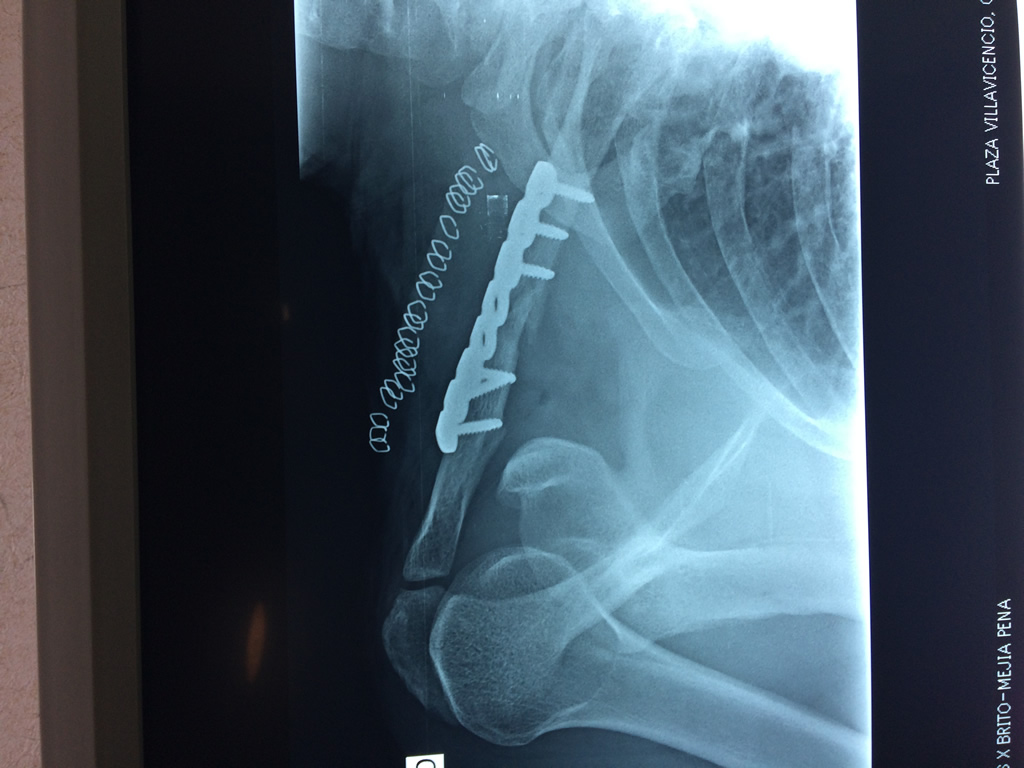

Cirugias en El Salvador - Clavícula